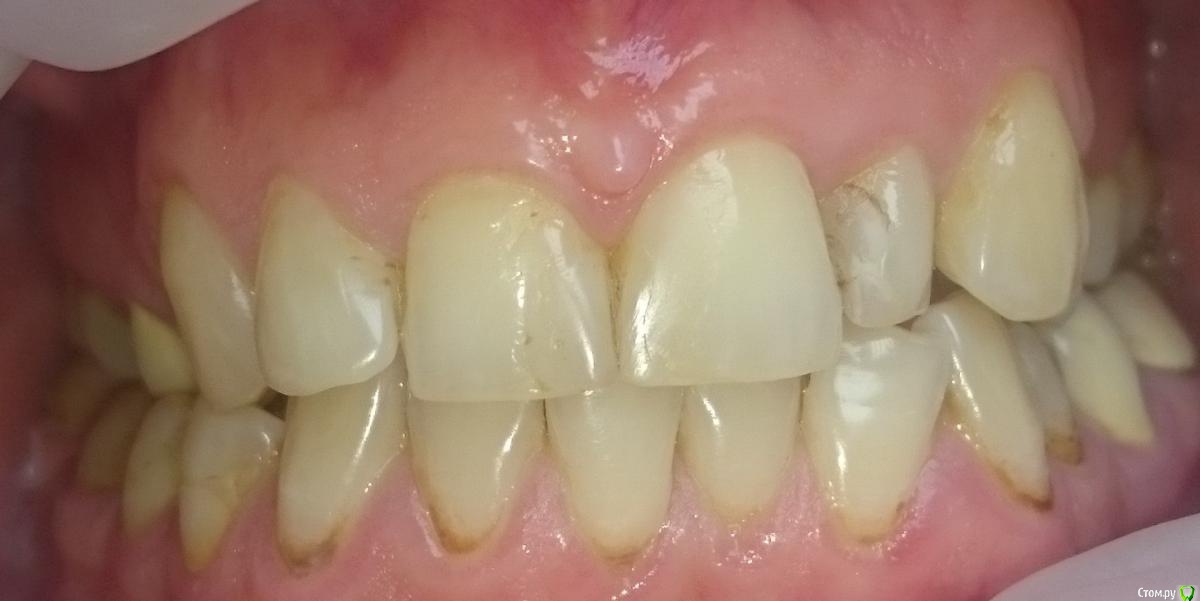

Metanira Опубликовано 17 апреля, 2015 Поделиться Опубликовано 17 апреля, 2015 Добрый день, дорогие стоматологи!Прилагаю снимок, сделанный в апреле этого года и фотографии. После него вылечена 4.4, так как вывалилась пломба. Очень хочу узнать ваше мнение по следующим вопросам и буду очень благодарна за любые ответы, не обязательно на все вопросы)Какие зубы стоит начать лечить в первую очередь? У меня очень много пломб, но менять их все не хочется, так как скоро от зубов ничего не останется( Пока планирую вылечить 2.1. В клинике к лечению посоветовали зубы: 14, 16, 17, 25, 26, 27, 34 (оверлей), 46 (оверлей), 47 (оверлей). С чего начать? Стоит ли пломбировать пришеечный кариес на нижних зубах? Врач рекомедовал лечить все зубы с 33 по 43. Они никак не беспокоят, боюсь лечить, так как боюсь, что появится чувствительность. Стоит ли пользоваться в моем случае монопучковой щеткой? Она у меня есть, но мне кажется, она все-таки жестковата. Что-то странное у меня с пломбой на 44-45 зубах сверху, она одна на 2 зуба, это как-то оправдано?) Какая щетка Cura Prox по вашему мнению лучше 5460 (один стоматолог сказал, что лучше ее использовать, так как чем мягче, тем лучше) или же 3960 (другой стоматолог посоветовал мне именно ее из-за сильного налета, после нее зубы кажутся белее, но боюсь, что для эмали она менее безопасна, чем 5460). Я курю и пью чай, зубы чищу регулярно, но вот такой вот налет. У меня щелкает правый сустав челюсти, стоит ли использовать Аква Сплинт или что-нибудь подобное ночью?Брекеты носить не планирую, так как мои зубы и эмаль этого точно не переживут.Заранее всех благодарю! Ссылка на комментарий

krokomot Опубликовано 17 апреля, 2015 Поделиться Опубликовано 17 апреля, 2015 Спасибо за ответ. Ошиблась, 2.2 как раз и хочу сделать в первую очередь. Эстетически меня вообще не беспокоит пришеечный кариес, поэтому если не стоит его трогать, то и не буду. Просто, как вы поняли, мне чуть ли не каждый зуб пломбировать или перепломбировывать, поэтому и хочу узнать, действительно ли все это необходимо или что-то можно не трогать. Ну и вопросы вроде довольно конкретные.... 1 решить сложно, что первее, не видя ситуации во рту, по ОПТГ ничего критичного не видно, там где в зубах пломбированы каналы стоит зделать прицельные снимки на придмет отсутствия околокорневой патологии. Так что думаю очередность на ваш выбор2. надо смотреть по ситуации если поврхностное поражение можно обойтись сошлифовыванием и полировкой затем минерализующая терапия и чувствительность, если она появиться - пройдет. А если процесс не поверхностный нужно реставрировать. Смысла в монопучковой щетке не вижу. Должна быть щетка средней жесткости, паста со фтором, правильная техника чистки зубов, зубная нить и ирригатор тогда с гигиеной проблем не будет, но надо делать профессиональную гигиену 2 раза в год.3. Пломб на 2 зуба быть не должно. И ответьте почему вы решили, что она на 2 зуба?4.Ответил в пункт 25. Шина возможно несколько улучшит ваше состояние, но проблемы с прикусом не решит, так что потихоньку готовтесь к иправлению прикуса. Ссылка на комментарий